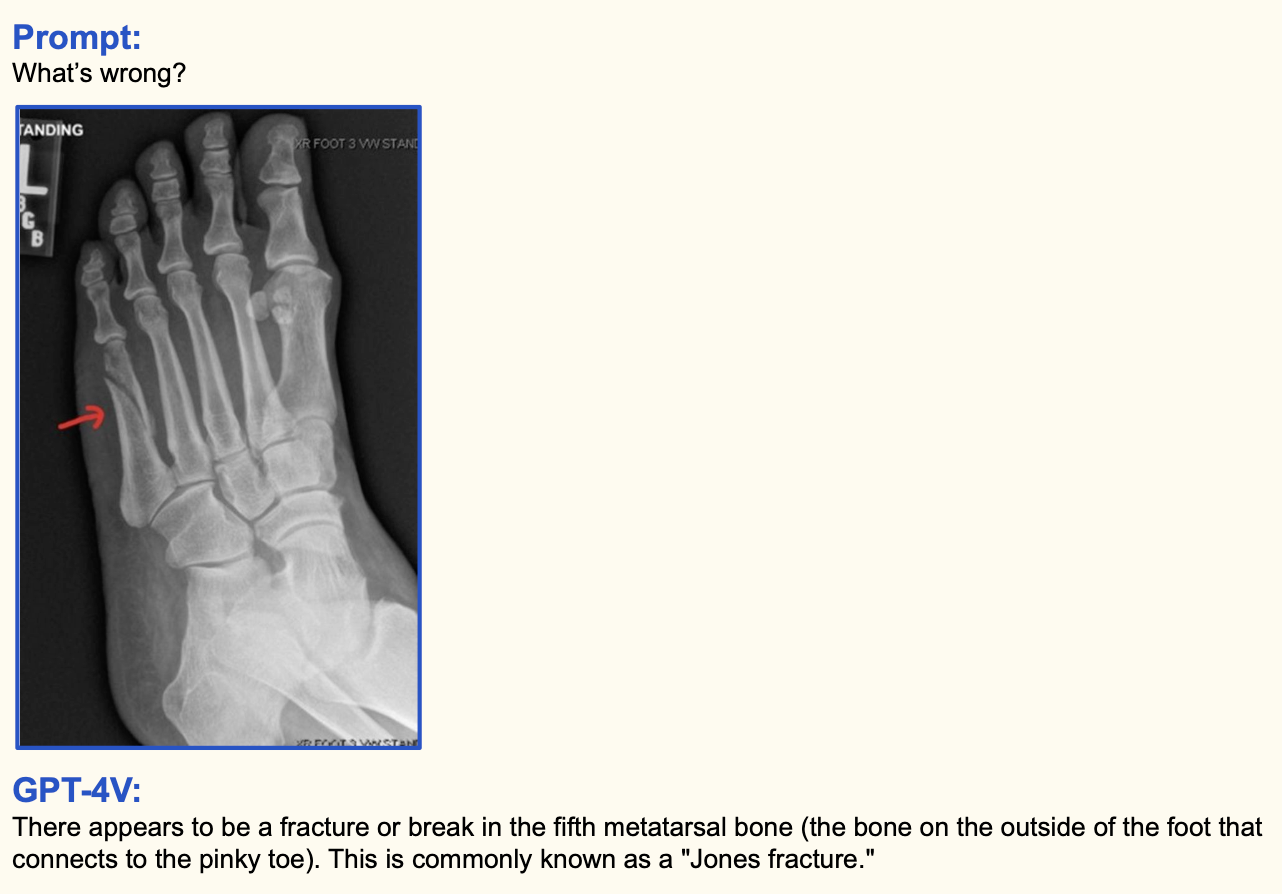

8. 의료 이미지 인식

신기하니까 몇 장 더보고 가겠습니다. 골절된 뼈 사진이랑 감염된 폐 CT 사진을 보여주고 무엇이 잘못됐는 설명해보라고 하면 잘 대답해줍니다. 대체 학습 데이터를 어떻게, 얼마나 많이 학습시켰길래 이렇게 잘나오는지 참... 대단합니다.

내용은 "GPT-4V 폼 미쳤다!" 한줄로 요약할 수 있을 것 같습니다. 전례없는 미친 성능을 보여주며 텍스트와 이미지의 경계를 깨버리네요. 특히 의료 이미지를 이해하고 전문적인 질문에 대답해주는 부분은 탄성을 자아냅니다.